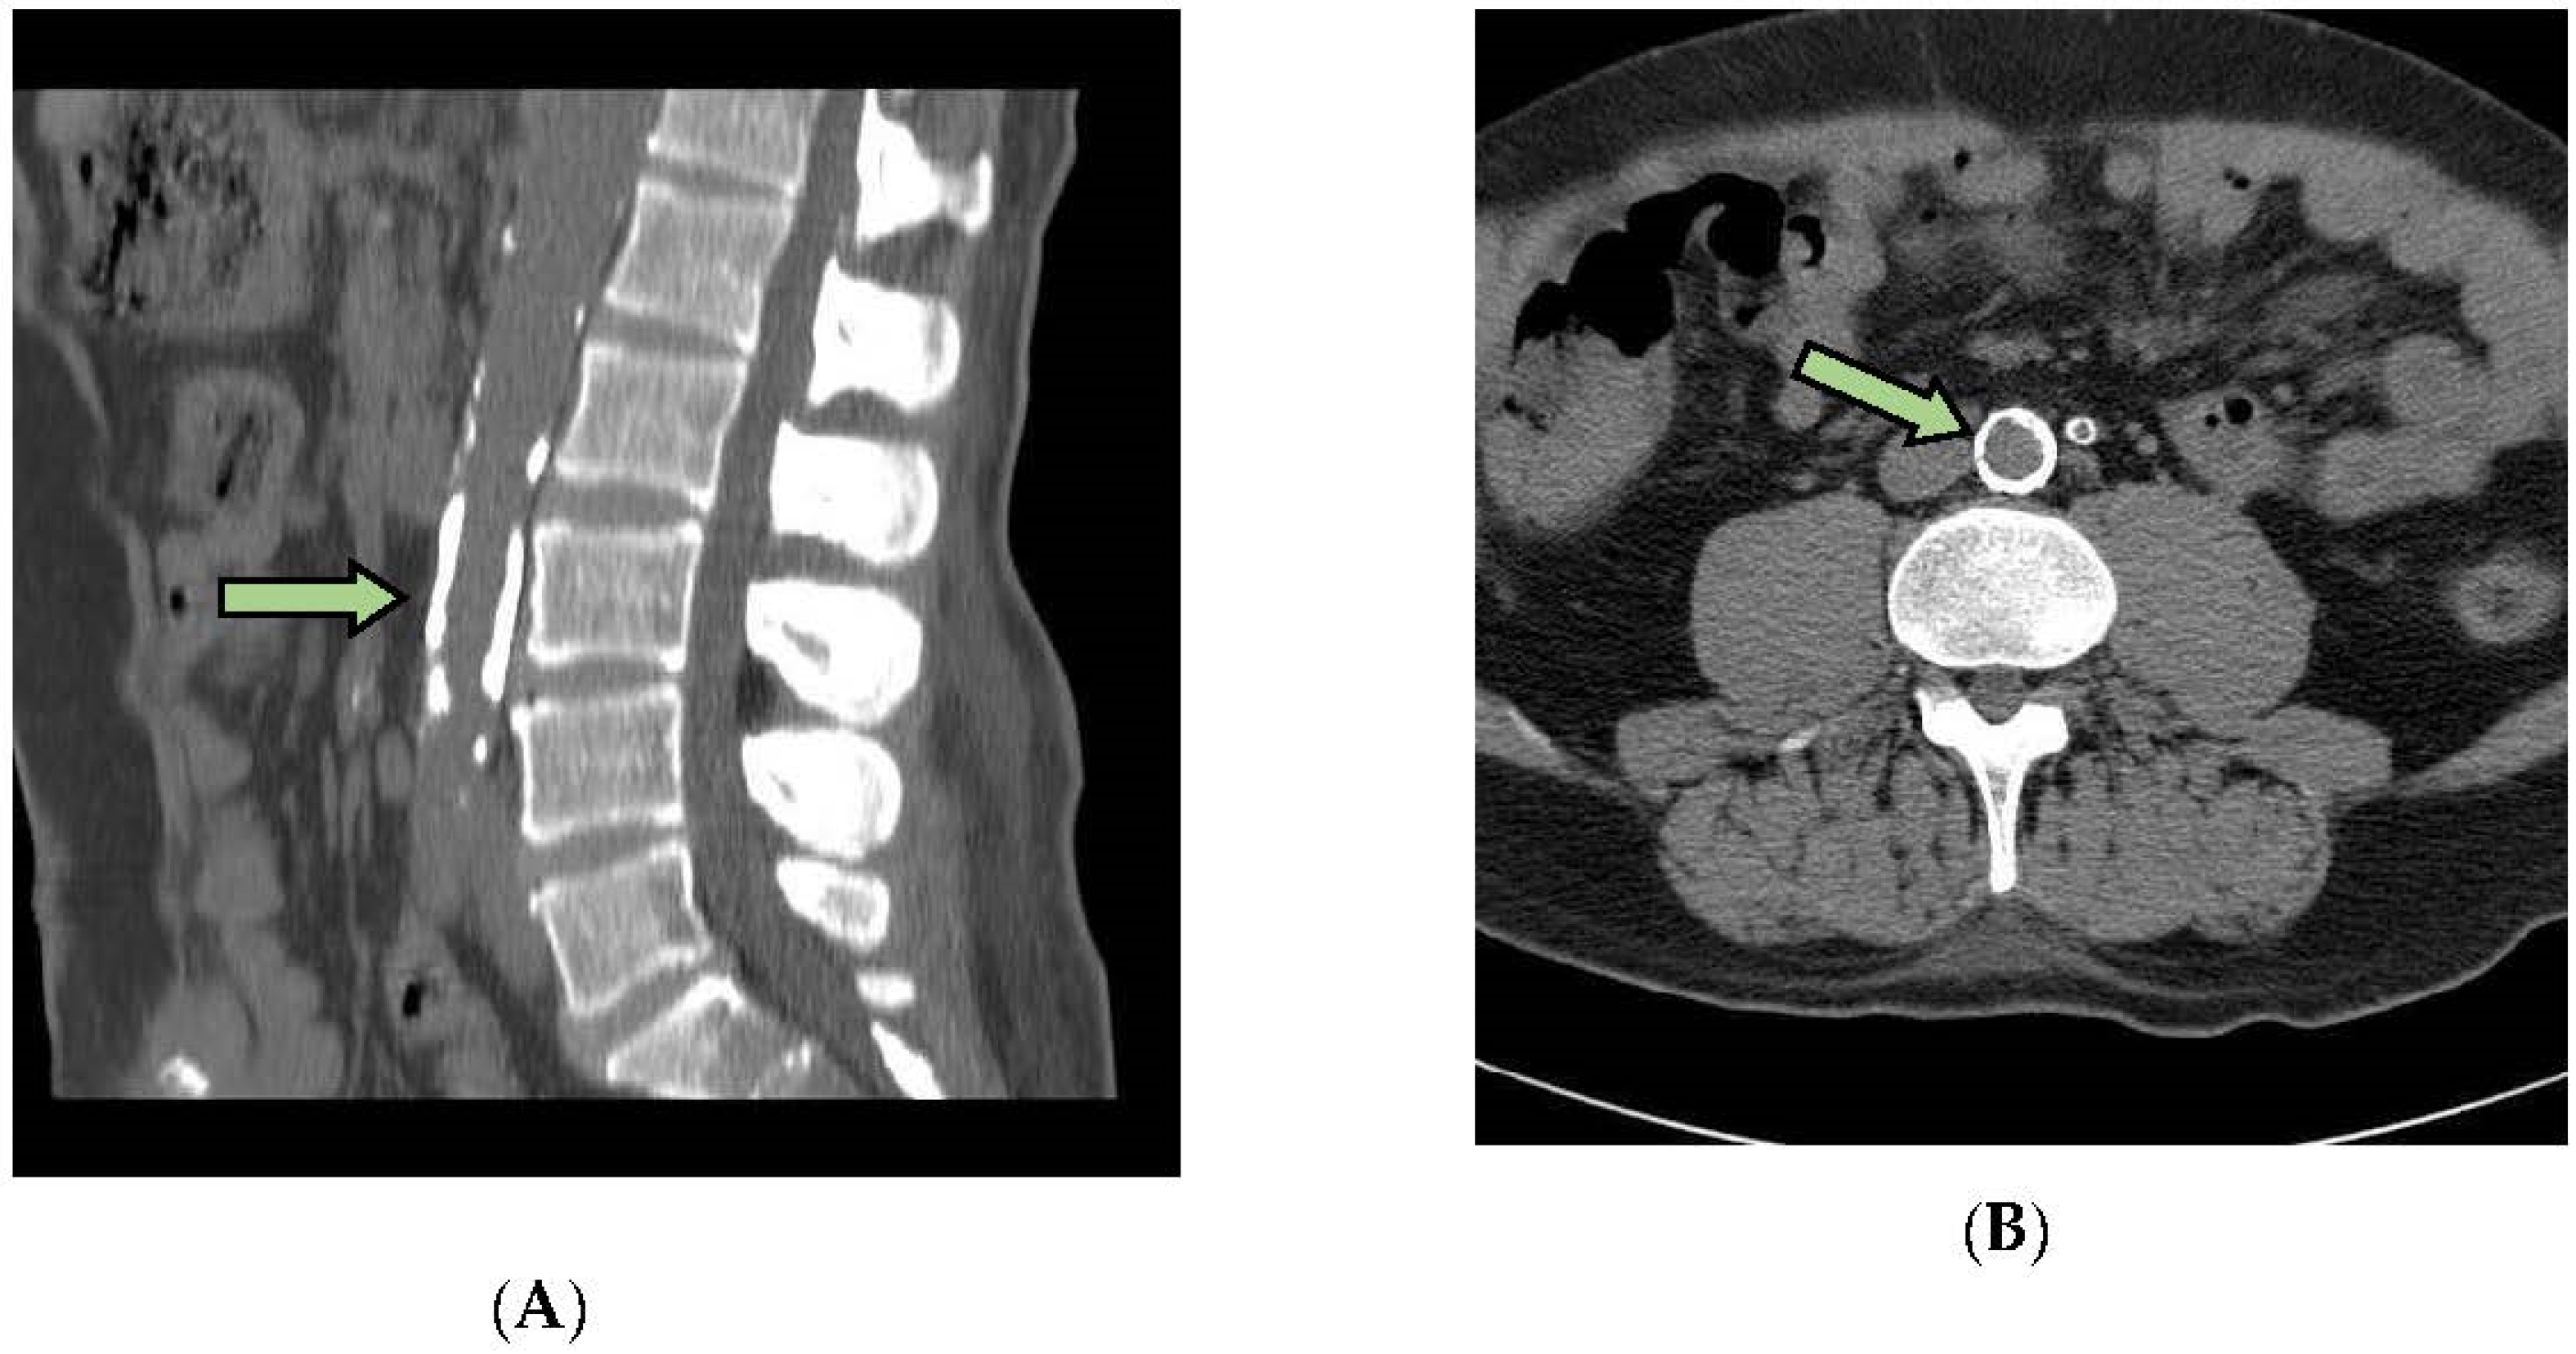

2.6. Measurement of Arterial Calcifications